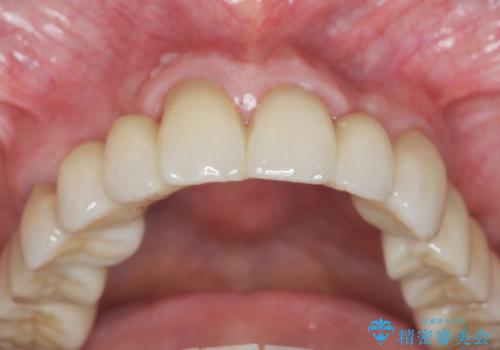

多発した虫歯による咬合崩壊 インプラントを用いた全顎治療

歯の破折・再発した大きな虫歯・根尖病変・歯の欠損、これらの問題を根管治療・歯周外科・インプラント治療・セラミック補綴を行うことで一つづつ解決し安定した咬合状となるよう治療を進めます。

口腔内全体を治療する全顎治療は、期間も長く外科を行う回数も多いためしっかりと通っていただくことが必要不可欠になります。

治療に加えて歯ブラシも上手になることが、治療した歯を長持ちさせるのに必要な要件となります。